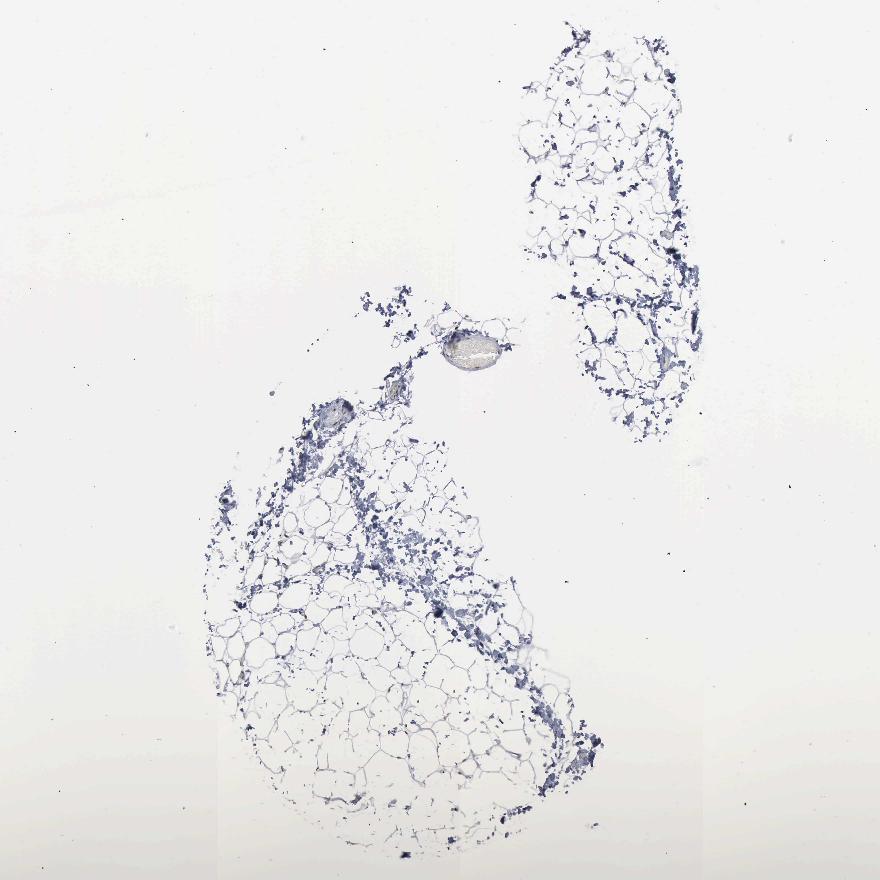

ADIPOSE TISSUE - Antibody stainingi

Antibody staining in the annotated cell types in the current human tissue is reported as not detected, low, medium, or high, based on conventional immunohistochemistry profiling in selected tissues. This score is based on the combination of the staining intensity and fraction of stained cells.

Each image is clickable and will lead to virtual microscopy that enables deeper exploration of all samples and also displays staining intensity scores, fraction scores and subcellular localization as well as patient and tissue information for each sample.

Antibody CAB000155

Adipocytes Medium